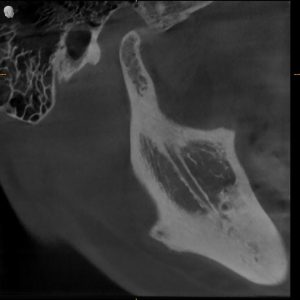

MRI confirmed bilateral disc displacement without reduction — both jaw joints had discs that had slipped out of position, causing compression and inflammation.

Clinical & Radiographic Findings

- Bilateral disc displacement without reduction

- Restricted opening (31 mm → improved to 47 mm)

- Myofascial tenderness and deep bite

- Significant parafunctional clenching pattern

Bilateral TMJ dysfunction with disc displacement and muscular hyperactivity.